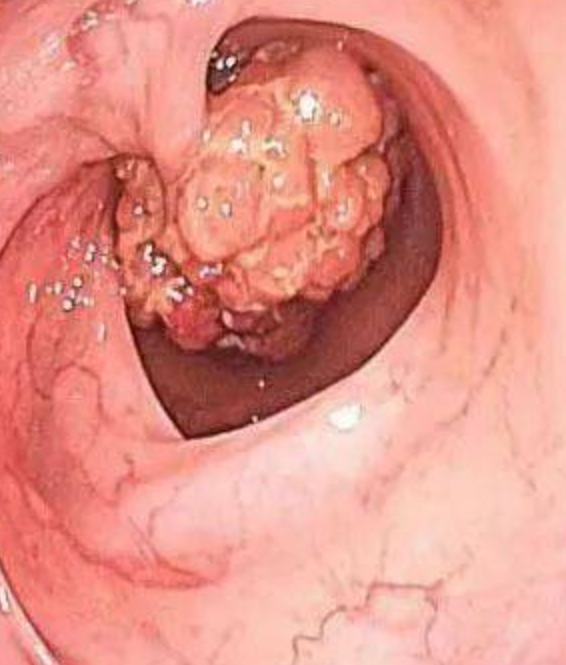

结果,不出所料,距肛门17-20cm处,一巨大菜花状占位性肿物,质硬脆,易

结肠镜:菜花样病变,阻塞肠腔.